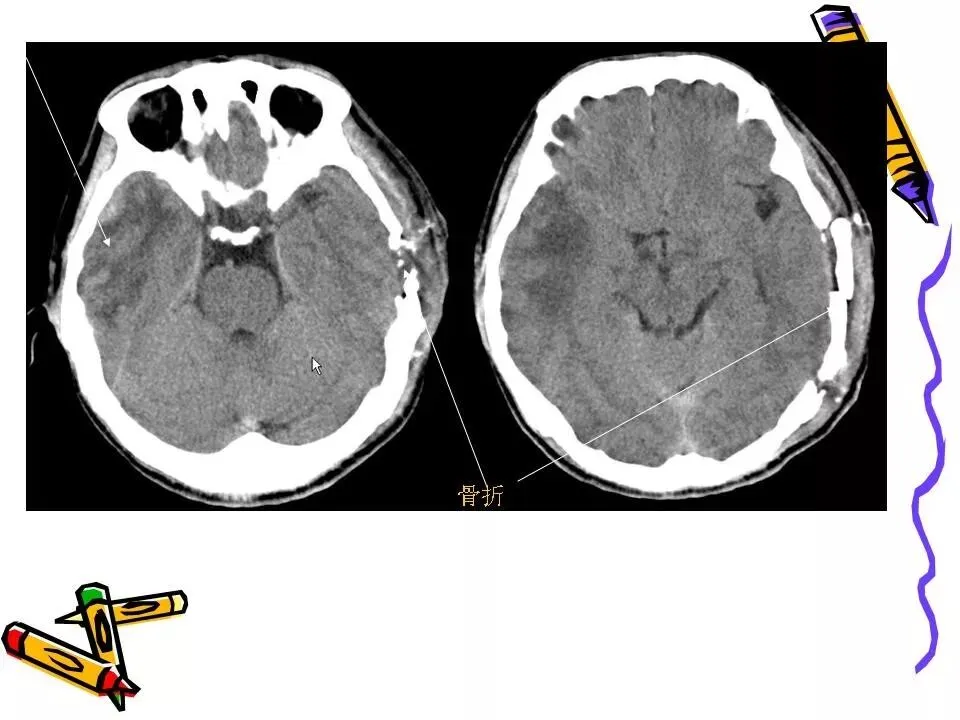

>常见颅脑外伤CT诊断(PPT)

常见颅脑外伤CT诊断(PPT)